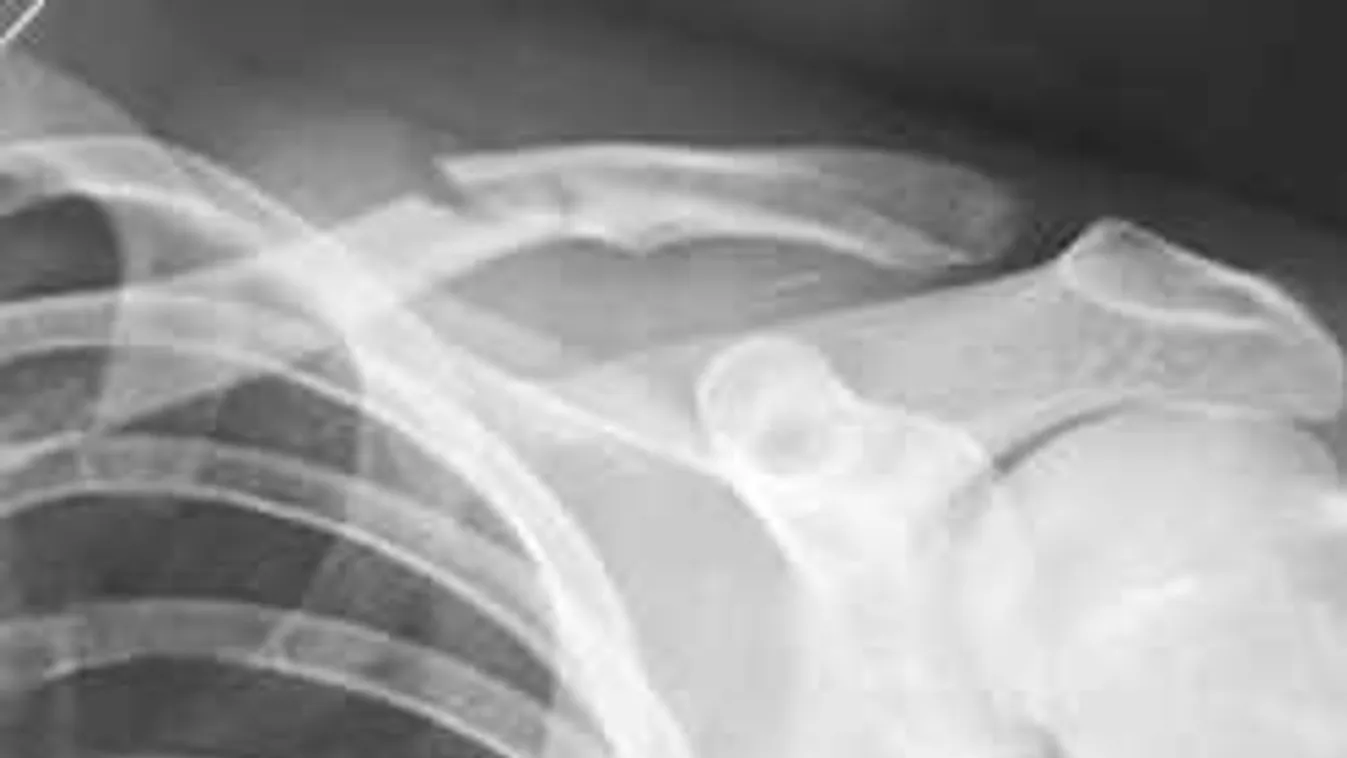

Az eredményt természetesen tálcán kínálta közel tízmilliós Instagram-táborának, sőt, a törött kulcscsontját is közszemlére tette.